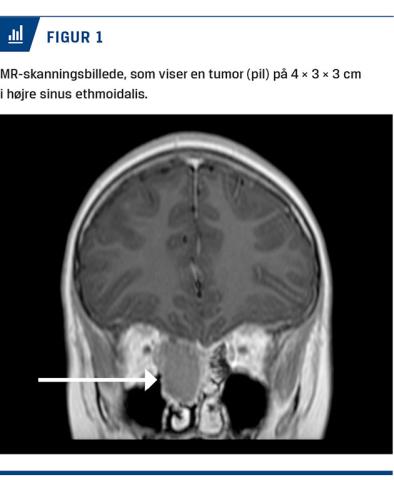

Før påbegyndelse af immunterapien blev han dog akut indlagt med hovedpine, nasalstenose, feber og smerter over højre kindben. På mistanke om purulent sinuitis blev der foretaget en MR-skanning, som viste en 4 × 3 × 3 cm stor tumor i højre sinus ethmoidalis (Figur 1). En histologisk undersøgelse viste FD. Den benigne tumor blev fjernet ved operation, hvilket medførte, at hovedpinen og smerterne over kindbenet forsvandt, samt at den nasale obstruktion blev lindret.